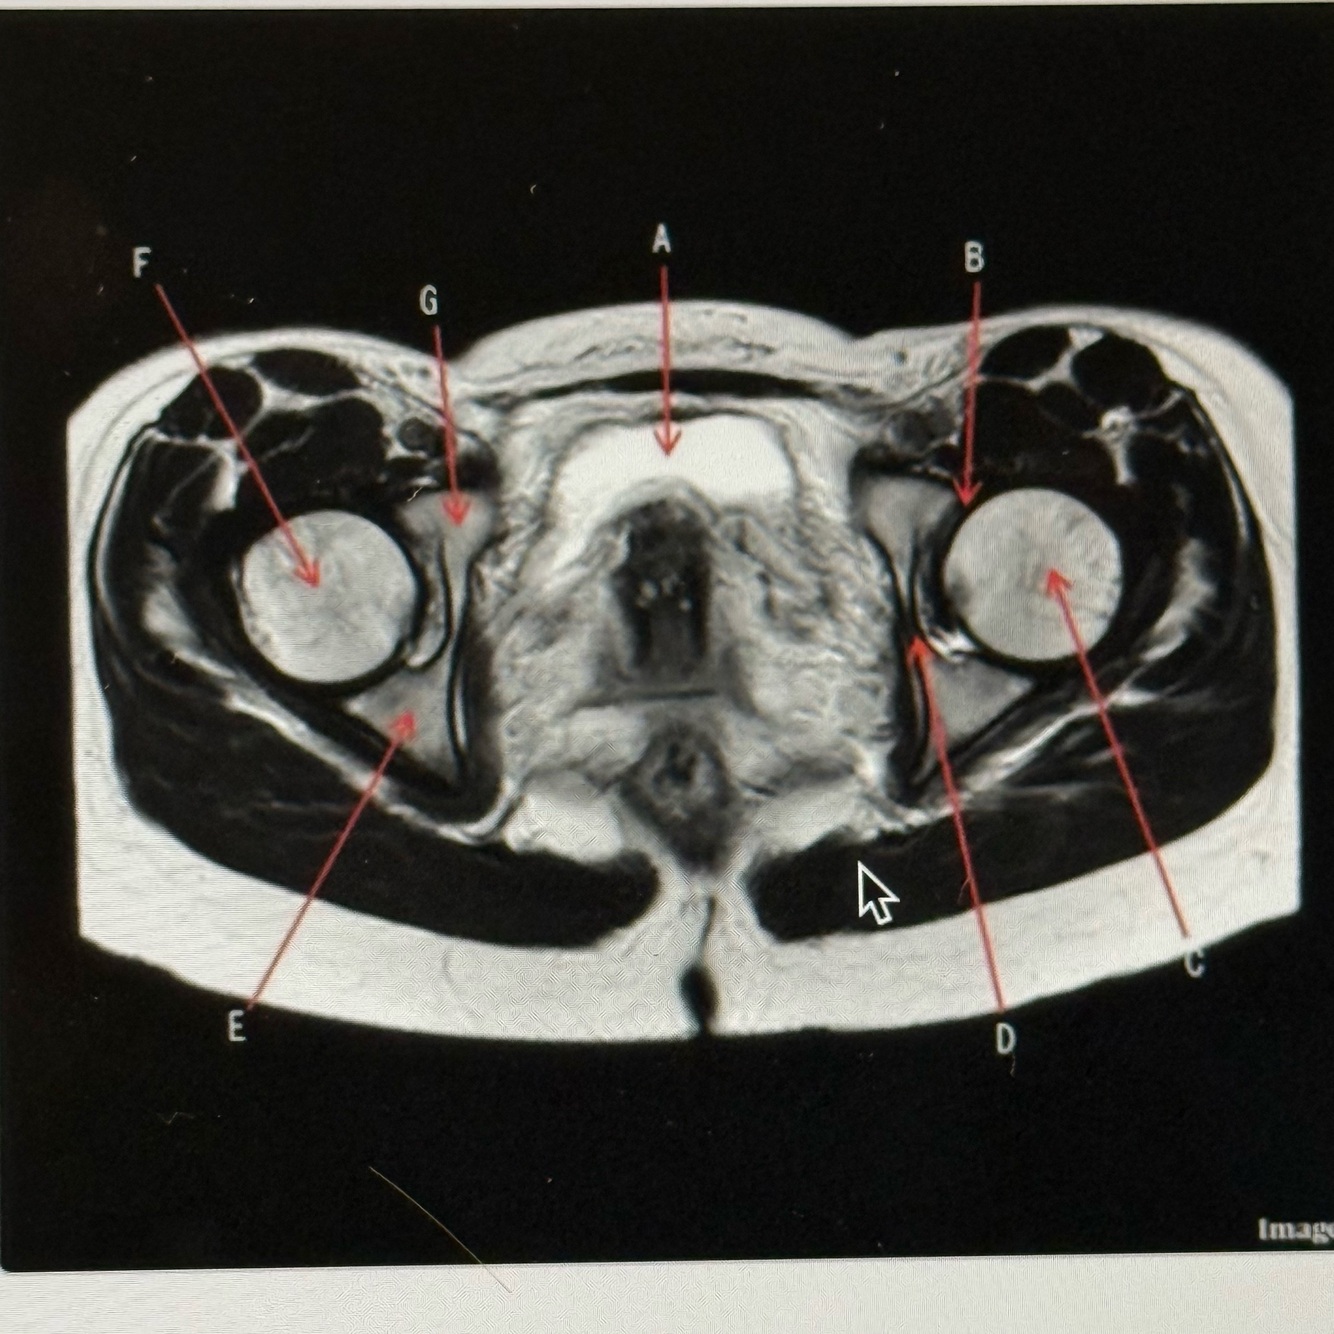

The image below is a ______ weighted image acquired in the _____ scan plane.

T2; Axial

Q

A

Bladder

Labrum